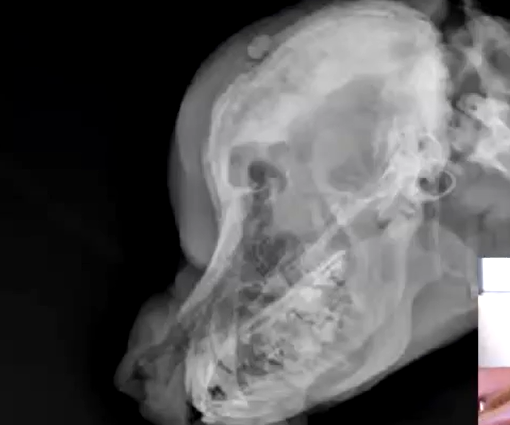

What are the radiographic signs of calvarial hyperostosis?

Marked thickening of frontal and parietal bones

Calvarial hyperostosis